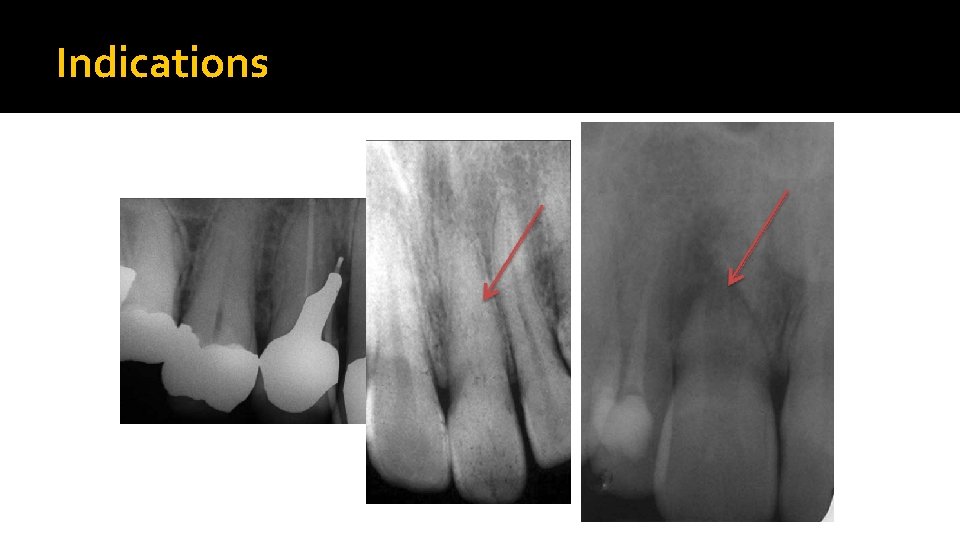

Endodontic Surgery Indications �Biopsy / drainage �No pulp space for Rx �Bizarre root configuration �Presence of post & core in the canal. �Breakage of Instrument in the canal. �Foreign bodies driven into the periapical area. �Perforation of the root. �Dental anomalies.

Indications